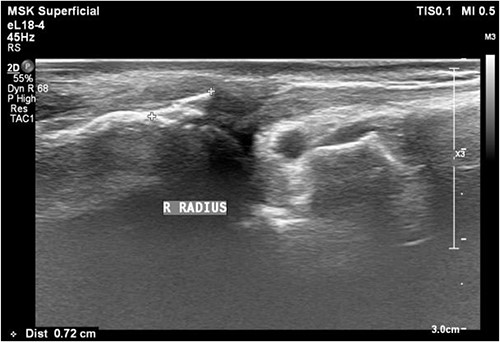

A 61-year-old male who denied any systemic disease, with a past medical history of a left distal radial fracture, which was treated with ORIF with a plate on 29 January 2017. He presented to the plastic surgery Outpatient Department (OPD) in July 2020 with a protruding mass over his left palmar wrist, which had been causing him pain for the past 3 weeks. On examination, poor flexion of the left thumb was noted. Upon suspicion of a ruptured FPL tendon, a sonogram was arranged, which confirmed the diagnosis (Fig. 1). After discussion with the patient, it was decided that he would undergo surgery.

Sonogram of the left wrist showing a ruptured FPL tendon. The arrow points to the discontinuity in the tendon, indicating the site of rupture.

A 35-year-old male with no significant medical history fell from a third-floor balcony while working in February 2022, resulting in a right distal radius fracture that was treated with volar plate fixation. However, during an outpatient visit in November 2022, he reported a right thumb weakness that had been present for 3–4 months. Right wrist X-ray showed fracture at distal radius and carpal bones, s/p internal fixation (Fig. 5). A sonogram revealed a right thumb flexor tendon injury (Fig. 6), and he was admitted to our orthopedic ward for surgical repair of the FPL rupture on 12 November 2022. During the operation, plastic surgeon was consulted to repair the FPL rupture with a PL graft, repair the radial artery rupture and vessel with graft, repair the carpal ligament with left tensor fascia lata, release scar contracture of the volar and dorsal carpal region, and perform neurolysis of the median nerve due to adhesion to the FPL tendon.

Sonogram of the right thumb showing an injured flexor tendon. Asymmetric fibrillar structures of the right FPL tendon were observed.